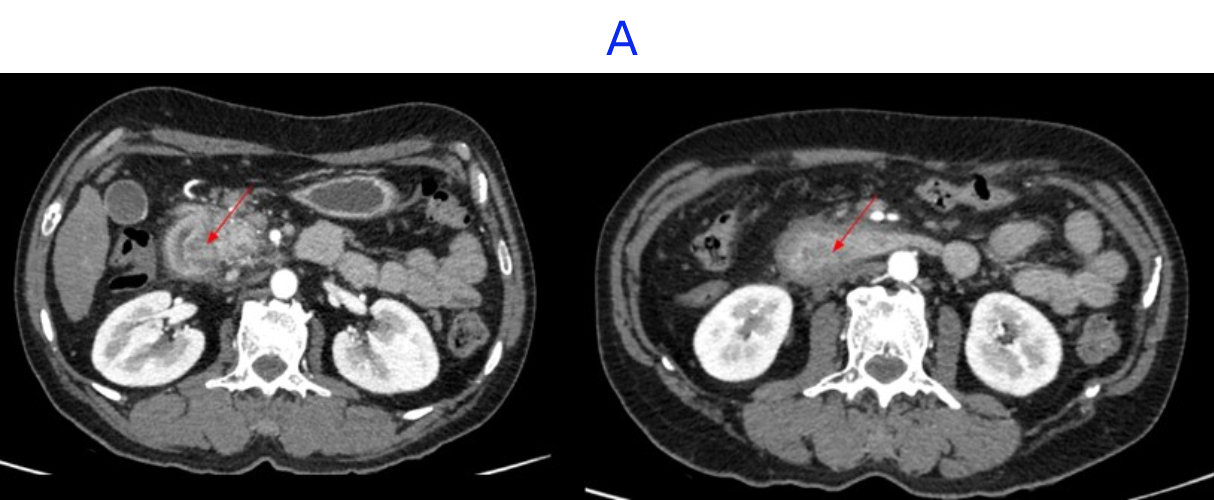

- A. Circumferential irregular submucosal wall thickening noted in D2 and D3 segment of duodenum causing luminal narrowing.